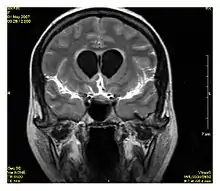

Neuroimaging

MRI is the investigative tool of choice for neurological cancers over CT, as it offers better visualization of the posterior cranial fossa, containing the brainstem and the cerebellum. The contrast provided between grey and white matter makes MRI the best choice for many conditions of the central nervous system, including demyelinating diseases, dementia, cerebrovascular disease, infectious diseases, Alzheimer's disease and epilepsy.[30][31][32] Since many images are taken milliseconds apart, it shows how the brain responds to different stimuli, enabling researchers to study both the functional and structural brain abnormalities in psychological disorders.[33] MRI also is used in guided stereotactic surgery and radiosurgery for treatment of intracranial tumors, arteriovenous malformations, and other surgically treatable conditions using a device known as the N-localizer.[34][35][36] New tools that implement artificial intelligence in healthcare have demonstrated higher image quality and morphometric analysis in neuroimaging with the application of a denoising system.[37]